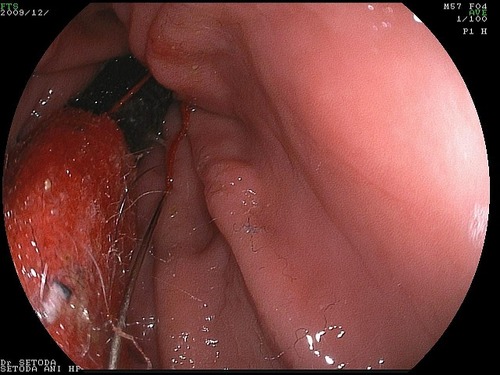

すぐに、全身麻酔をほどこし、内視鏡で取り出す手術を始めました。

胃の中の針はすぐに見つけ出すことが出来ましたが、他にも何か胃の中にあるようです。